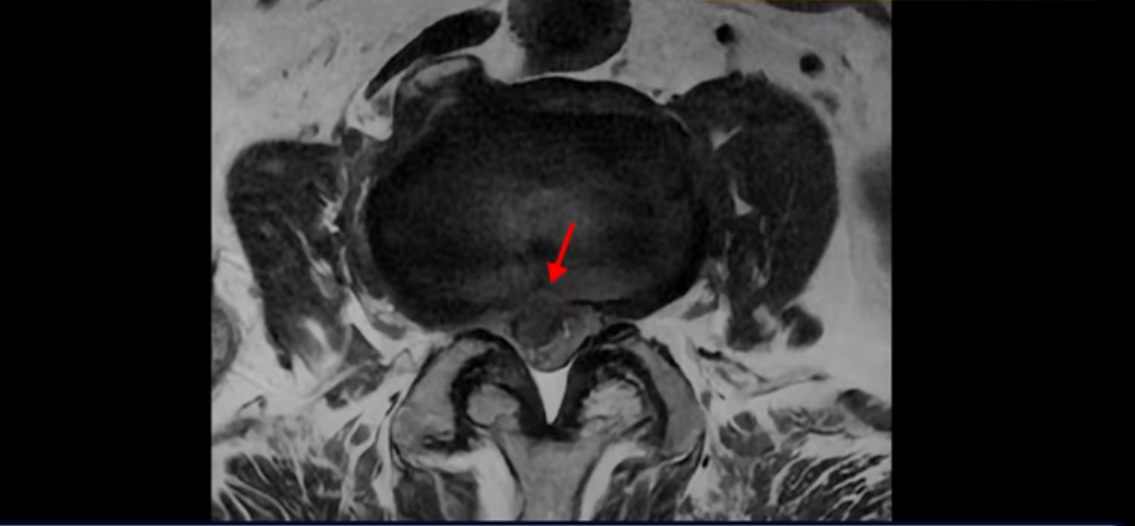

기립근의 지방화도 심합니다. 또 3번 4번 마디에서는 신경가지가 빠져나가는 추간공이 왼쪽, 오른쪽 모두 많이 좁아져 있습니다.

이런 이유로 이 환자분은 왼쪽 다리는 마비가 생겨 힘이 빠지고 오른쪽 다리에는 심한 방사통이 있어서 휠체어까지 타야 하는 상태가 되었습니다. 이렇게 심하니까 대학병원에서 여러 마디 나사를 박는 유합술을 권유 받으셨는데요.